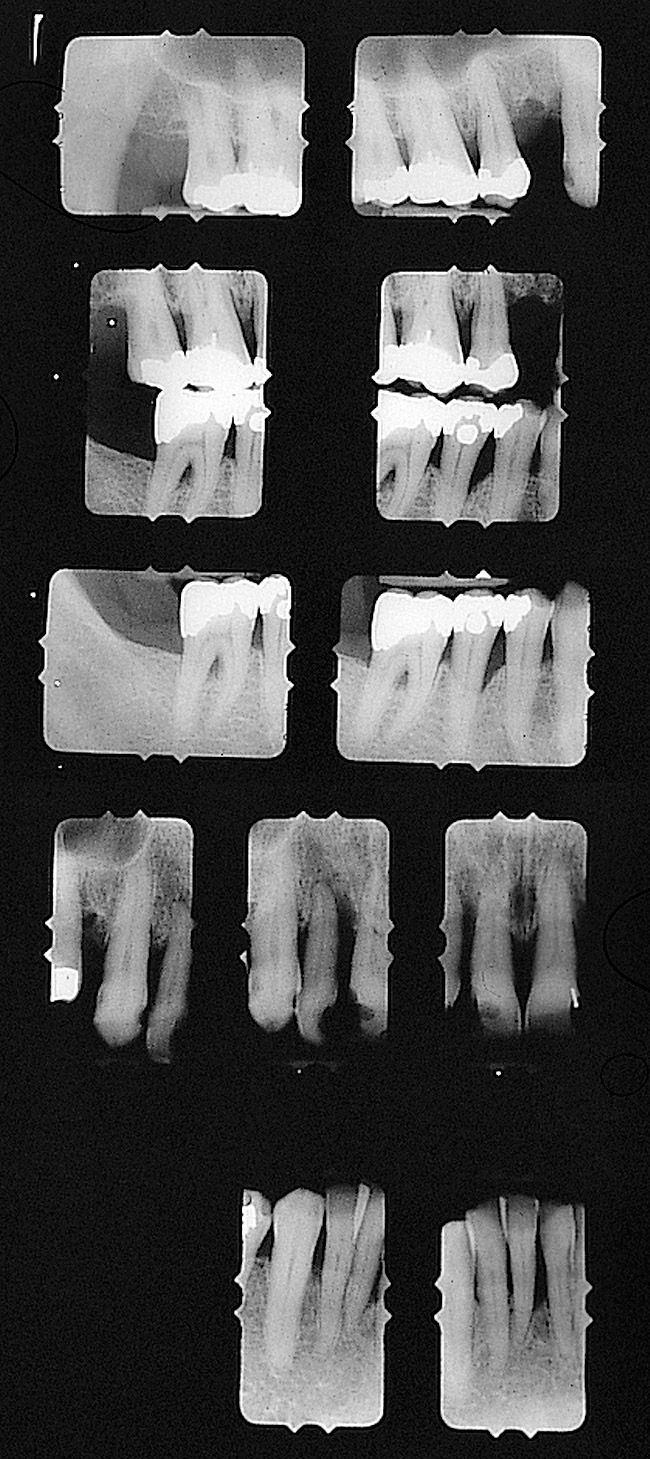

Figure 16  Preoperative radiographic view, right side.

Figure 16

Figure 17  Preoperative radiographic view, left side.

Figure 17